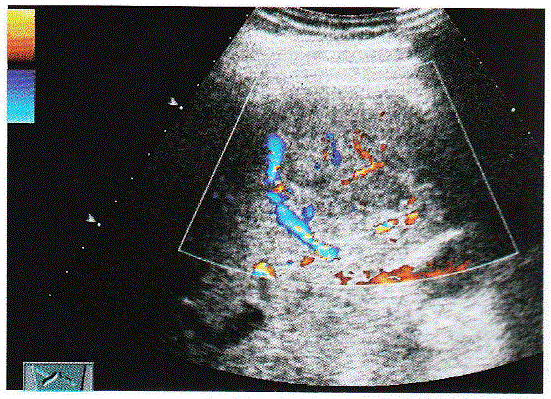

问题 临床资料:男,41岁;自述明显消瘦、腹胀、食欲不振;患慢性乙型肝炎18年, 化验检查:AFP增高。 超声综合描述:肝表面不平,回声明显不均,有结节感,部分结节互相融合,肝中裂增宽,三支肝静脉变细,门静脉内径1.6cm,肝右叶可见7.1cm×4.2cm低回声区,内回声不均,CDFI:低回声内可见动静脉血流信号,周边可见血管绕行。见下图及彩图。 {图1} 超声提示:

选项 A.肝硬化 B.肝癌 C.门静脉增宽 D.以上各项均是

答案 D